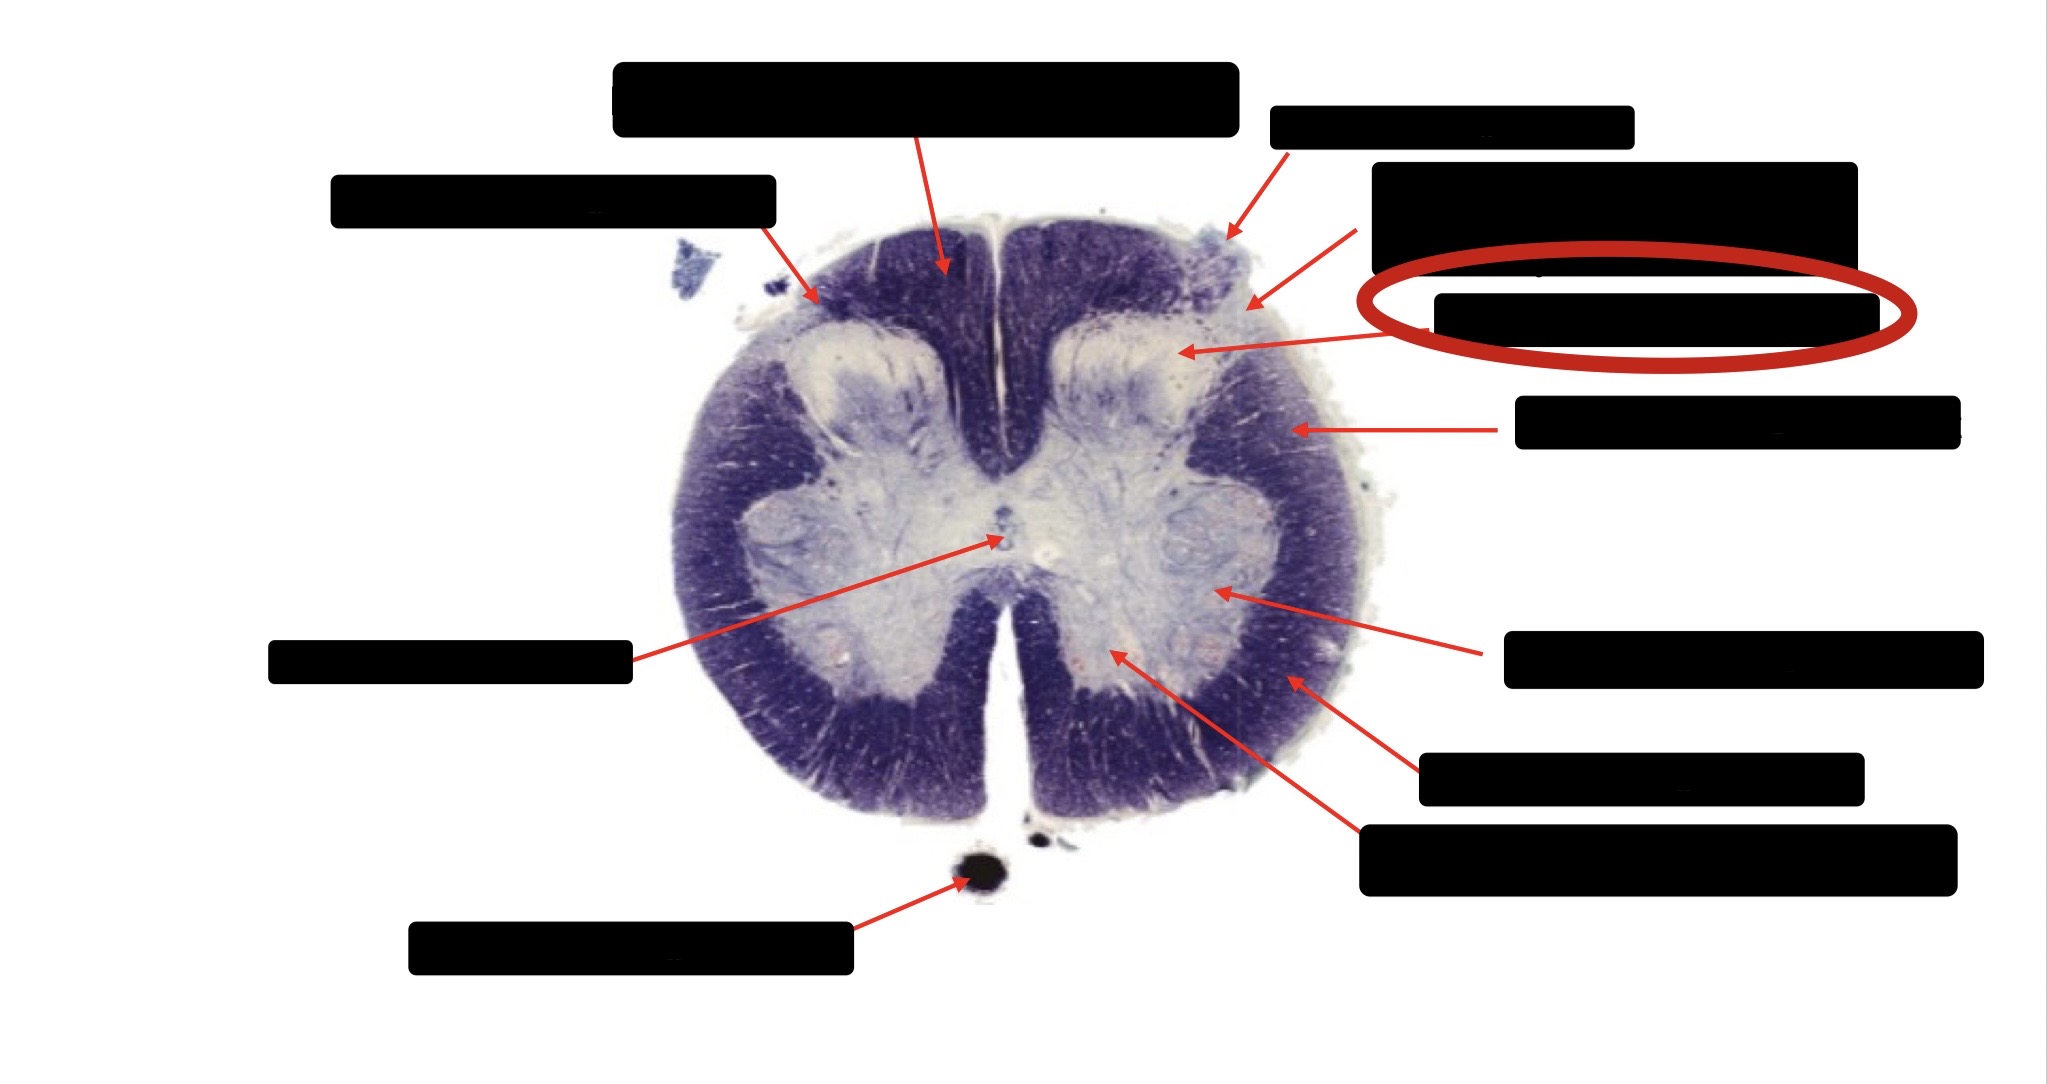

Spinothalmic Tract

Central Canal

Posterior Column (Fasciculus Gracilis)

Large Fiber Entry Zone

Lissaeur’s Tract & Small Fiber Entry Zone

Substantia Gelatinosa

Lateral Corticospinal Tract

Ventral Root Fibers

Anterior Horn Motor Neurons

Anterior Medial Fissure

Dorsal Rootlet

Posterior Spinocerebellar Tract

Anterior Spinocerebellar Tract

Posterior Column (Fasciculus Cuneatus)

Anterior Horn Motor Neurons (Distal Muscles)

Anterior Horn Motor Neurons (Proximal Muscles)

Anterior Corticospinal Tract